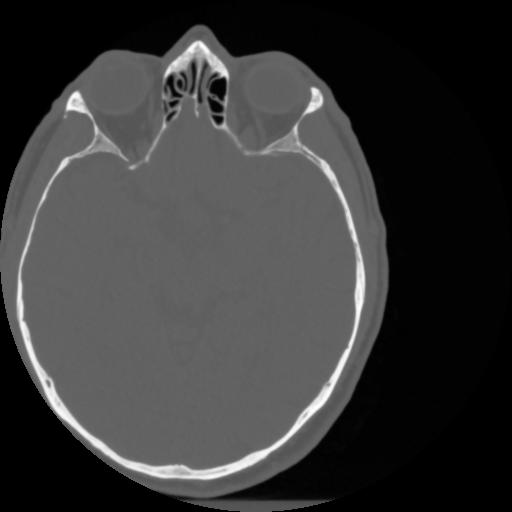

4 CEREBRO,,Vol,0.5,CEREBRO,,